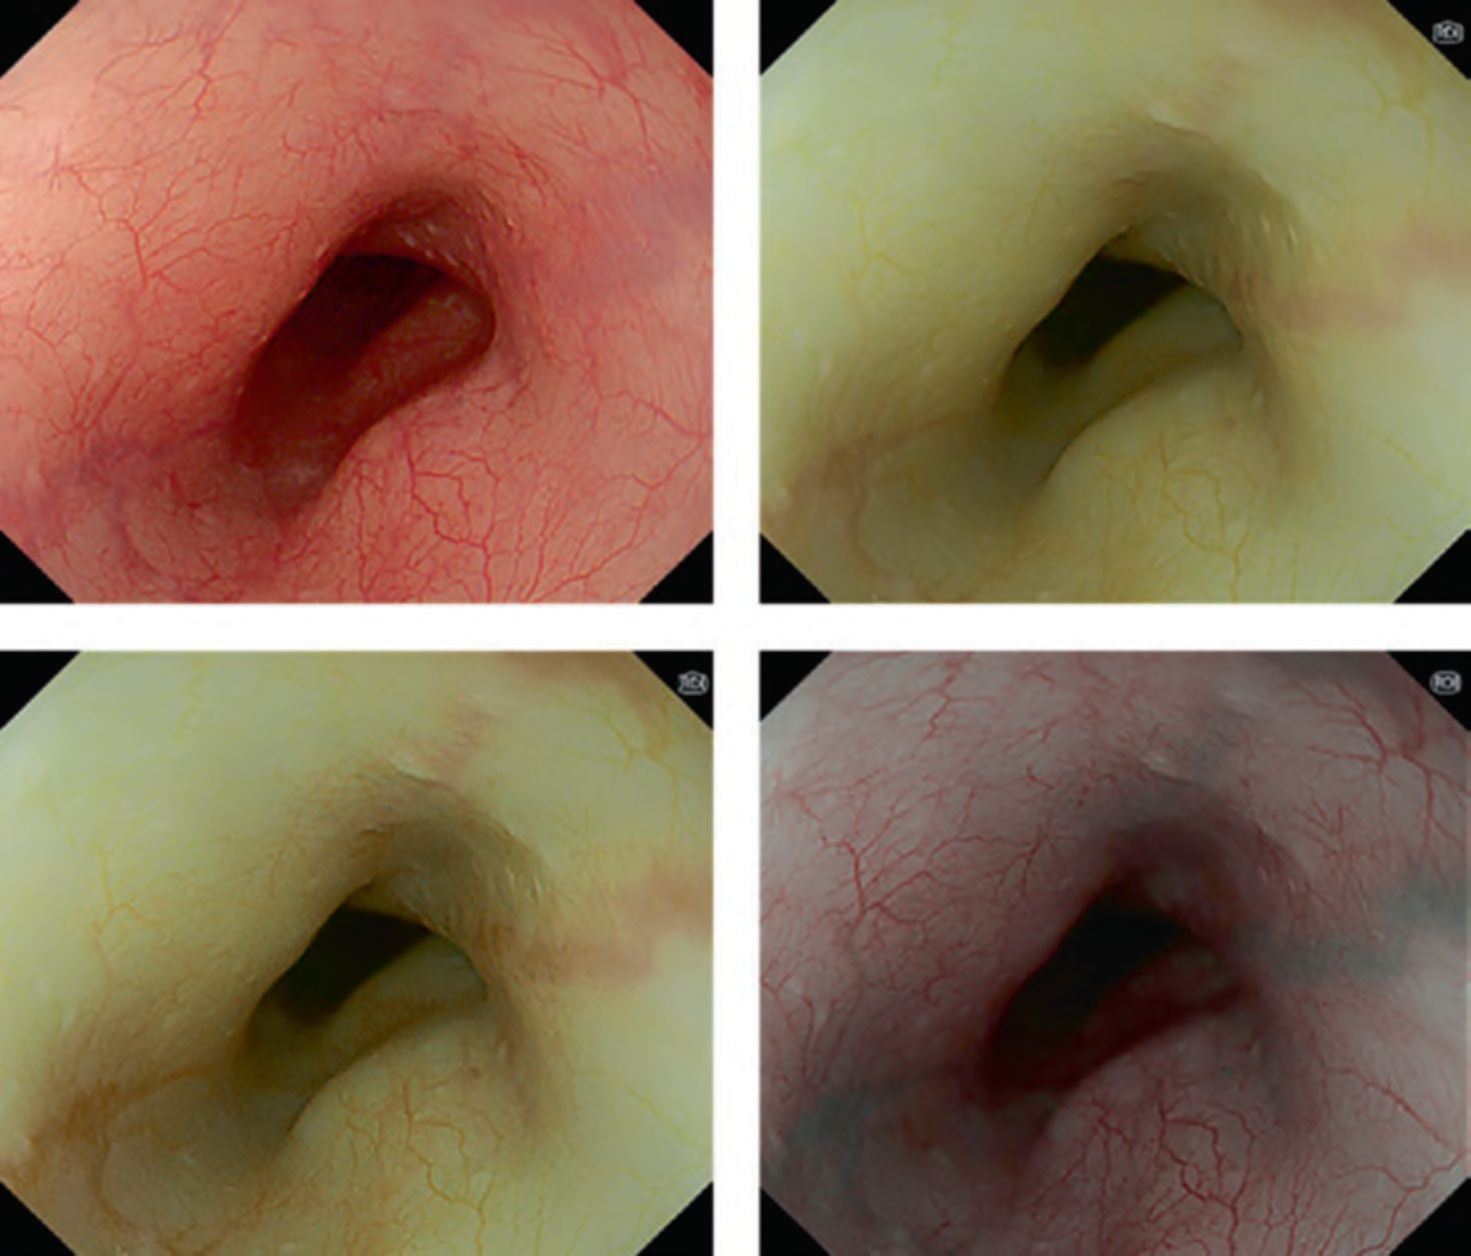

The working group members carried out a systematic review of the English literature to determine widely accepted diagnostic systems. Consequently, the best-accepted diagnostic system was proven to be the VS classification system. Based on this system, MESDA-G was constructed using an evidence-based approach (. Figs. 3, 4, 5, and 6) [2]. First, lesions suspicious for EGC should be detected by careful inspection using conventional white-light endoscopy. Subsequently, magnified observations should be performed. Owing to the high sensitivity of the demarcation line [8], if it is absent, the suspicious lesion is diagnosed as noncancerous (. Fig. 4a, b). However, if the demarcation line is present, further assessment is required to determine the presence of an irregular MV or MS pattern. If an irregular MV and/or MS pattern is detected, the suspicious lesion is diagnosed as cancerous (. Fig. 6a, b) [1, 5, 6, 8]. If both the irregular MV and MS patterns are absent, the tumor is diagnosed as noncancerous (. Fig. 5a, b) [1, 5, 6, 8].